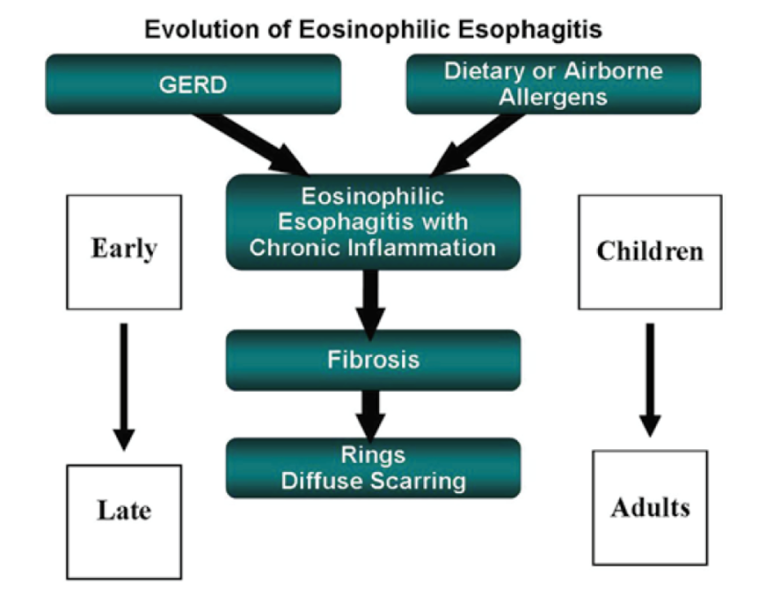

이 염증반응에 의해 혈관의 신생합성이 증가하여 근육층이 두꺼워지고 섬유화가 진행되어 식도의 운동성을 저하시키고 내강이 좁아지는 담보이기 때문에 음식통과를 위한 경로가 적어집니다.

경과기 전에 말씀드렸다시피 먼저 호산구 식도염의 초기 증상은 염증 반응입니다. 이 염증 반응은 치료하지 않을 경우 esophageal remodling을 통해 내강이 좁아지고 기능 저하가 발생합니다. 하지만 항염증 요법을 시행할 경우, 호산구 식도염 질병의 진행 결과를 제한할 수 있다는 일부 보고가 발표되었습니다.이를 바탕으로 질병 발생 초기 또는 소아 청소년에서 발생한 호산구 식도염의 경우 약물치료 또는 식사치료를 할 수 있으나 이미 병변이 진행 중이고 섬유화가 진행된 경우 식도확장시술 외에는 다른 약물, 식생활료요법이 효과적이지 않습니다.

요약 정리하면 호산구 식도염은 전형적인 식도 증상과 식도 조직 검사를 통해 얻은 병변의 특징으로 진단되며 GERD, 감염, 크론병과 같은 식도 내 호산구를 증가시키는 질환을 제거해야 합니다. 호산구 식도염은 감수성이 있는 사람에게 항원에 노출되면 나타나는 면역 반응입니다. 특히 호산구 식도염에서 음식물의 역할은 호산구 식도염의 병태 메커니즘과 호산구 식도염을 치료하는데 중요합니다. 치료에 대해서는 다음 포스팅에서 구체적으로 이야기할 예정입니다.호산구 식도염의 경과는 아직 분명치 않지만 치료하지 않을 경우 질병의 지속과 함께 식도섬유화가 발생하고 섬유화 단계에서는 식도확장시술 외에는 다른 치료방법이 없기 때문에 조기 발견 및 치료하는 것이 중요합니다.